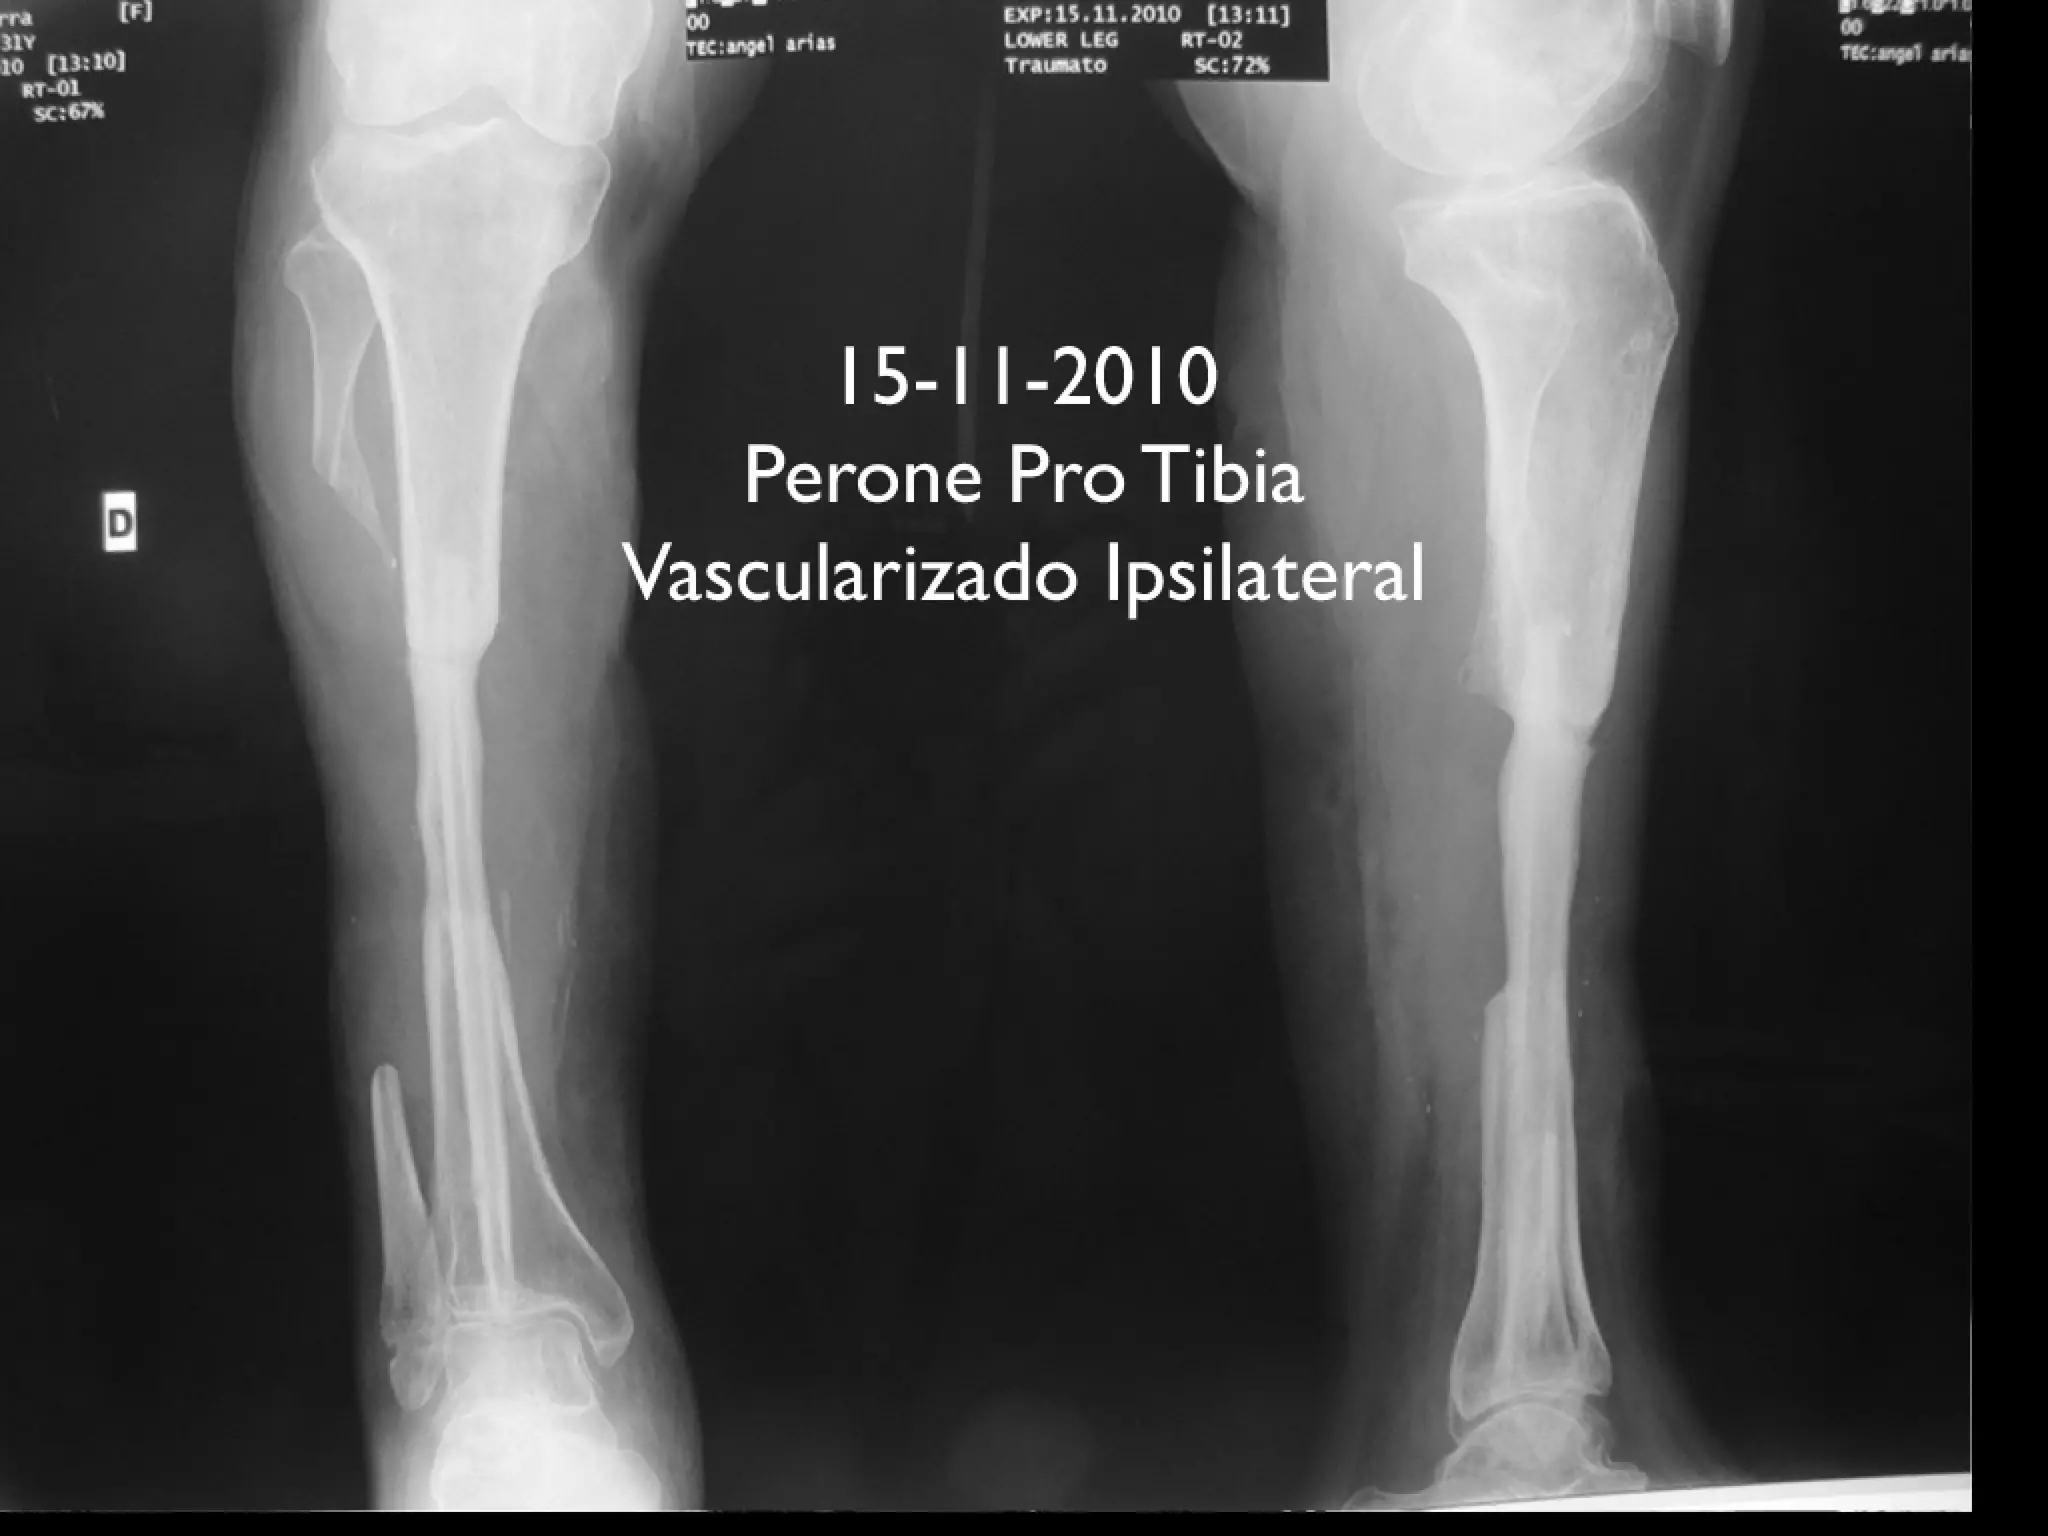

Perone pro Tibia Vascularizado Ipsilateral | PDF